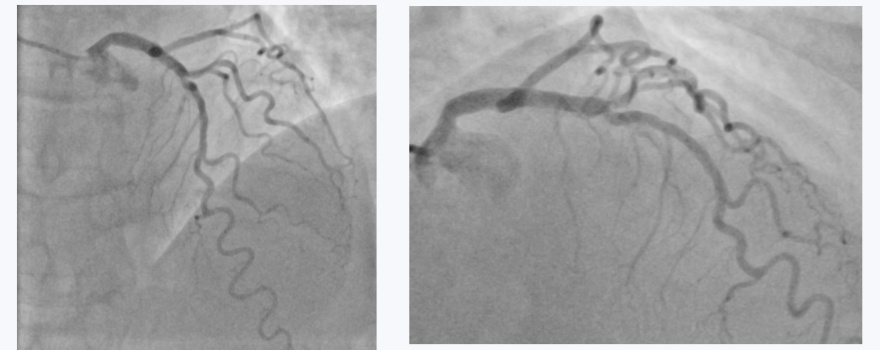

导丝顺利通过闭塞段后,选用Medoo MeCross CTO半顺应性PTCA球囊扩张导管1.0mm 球囊进行初始病变预处理,球囊无阻力通过闭塞段并精准定位,充气后扩张充分,为后续器械操作奠定良好基础。整个手术过程中,Medoo球囊拆封简便、充放气顺畅稳定无延迟,无任何操作障碍,产品整体性能与国际一线品牌持平,助力手术顺利完成,最终造影显示病变部位血流通畅,效果优异。

手术选用Medoo MeCross NC 非顺应性PTCA球囊扩张导管3.0×15mm对钙化病变进行预扩张,球囊轻松通过重度钙化狭窄部位,定位精准无偏差,充放气过程顺畅可控,推送性与跟踪性表现优异。

在Medoo球囊高效预扩张的基础上,术者顺利完成主支支架植入、后扩张及对角支病变处理,最终造影显示分叉部位血流通畅,无残余狭窄,手术效果极佳。Medoo球囊全程无任何使用缺陷,再次验证了产品的稳定表现。